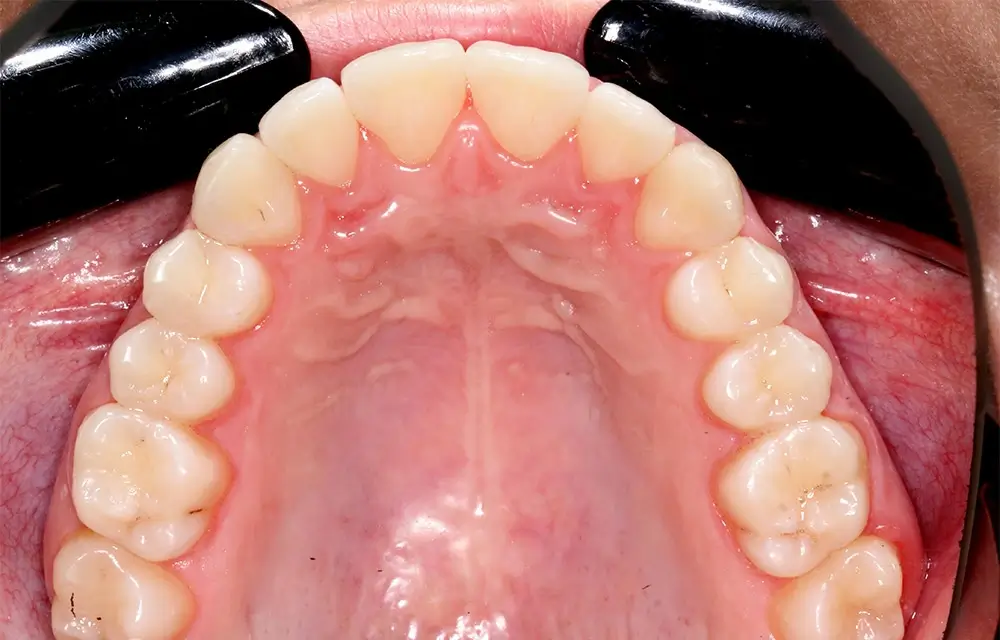

Скученность - Кейс 10

Эффективность устранения дефекта прикуса посредством элайнеров FlexiLigner.

16

Количество кап НЧ

Количество кап ВЧ

Результаты лечения